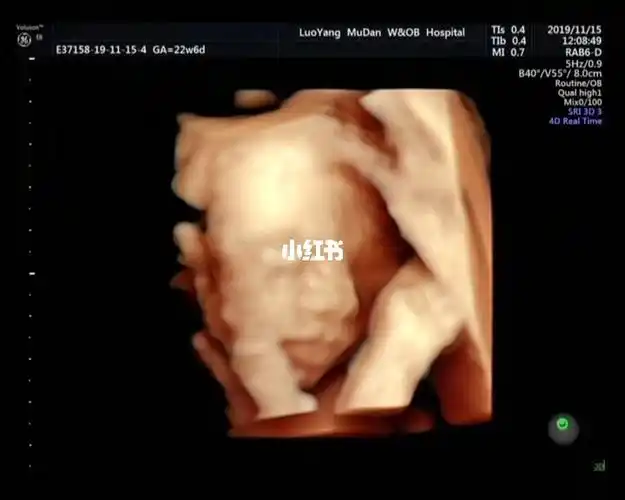

刚看到四维的时候我跟孩他爸都惊呆了,大鼻子,厚嘴唇,感觉还有点腭裂